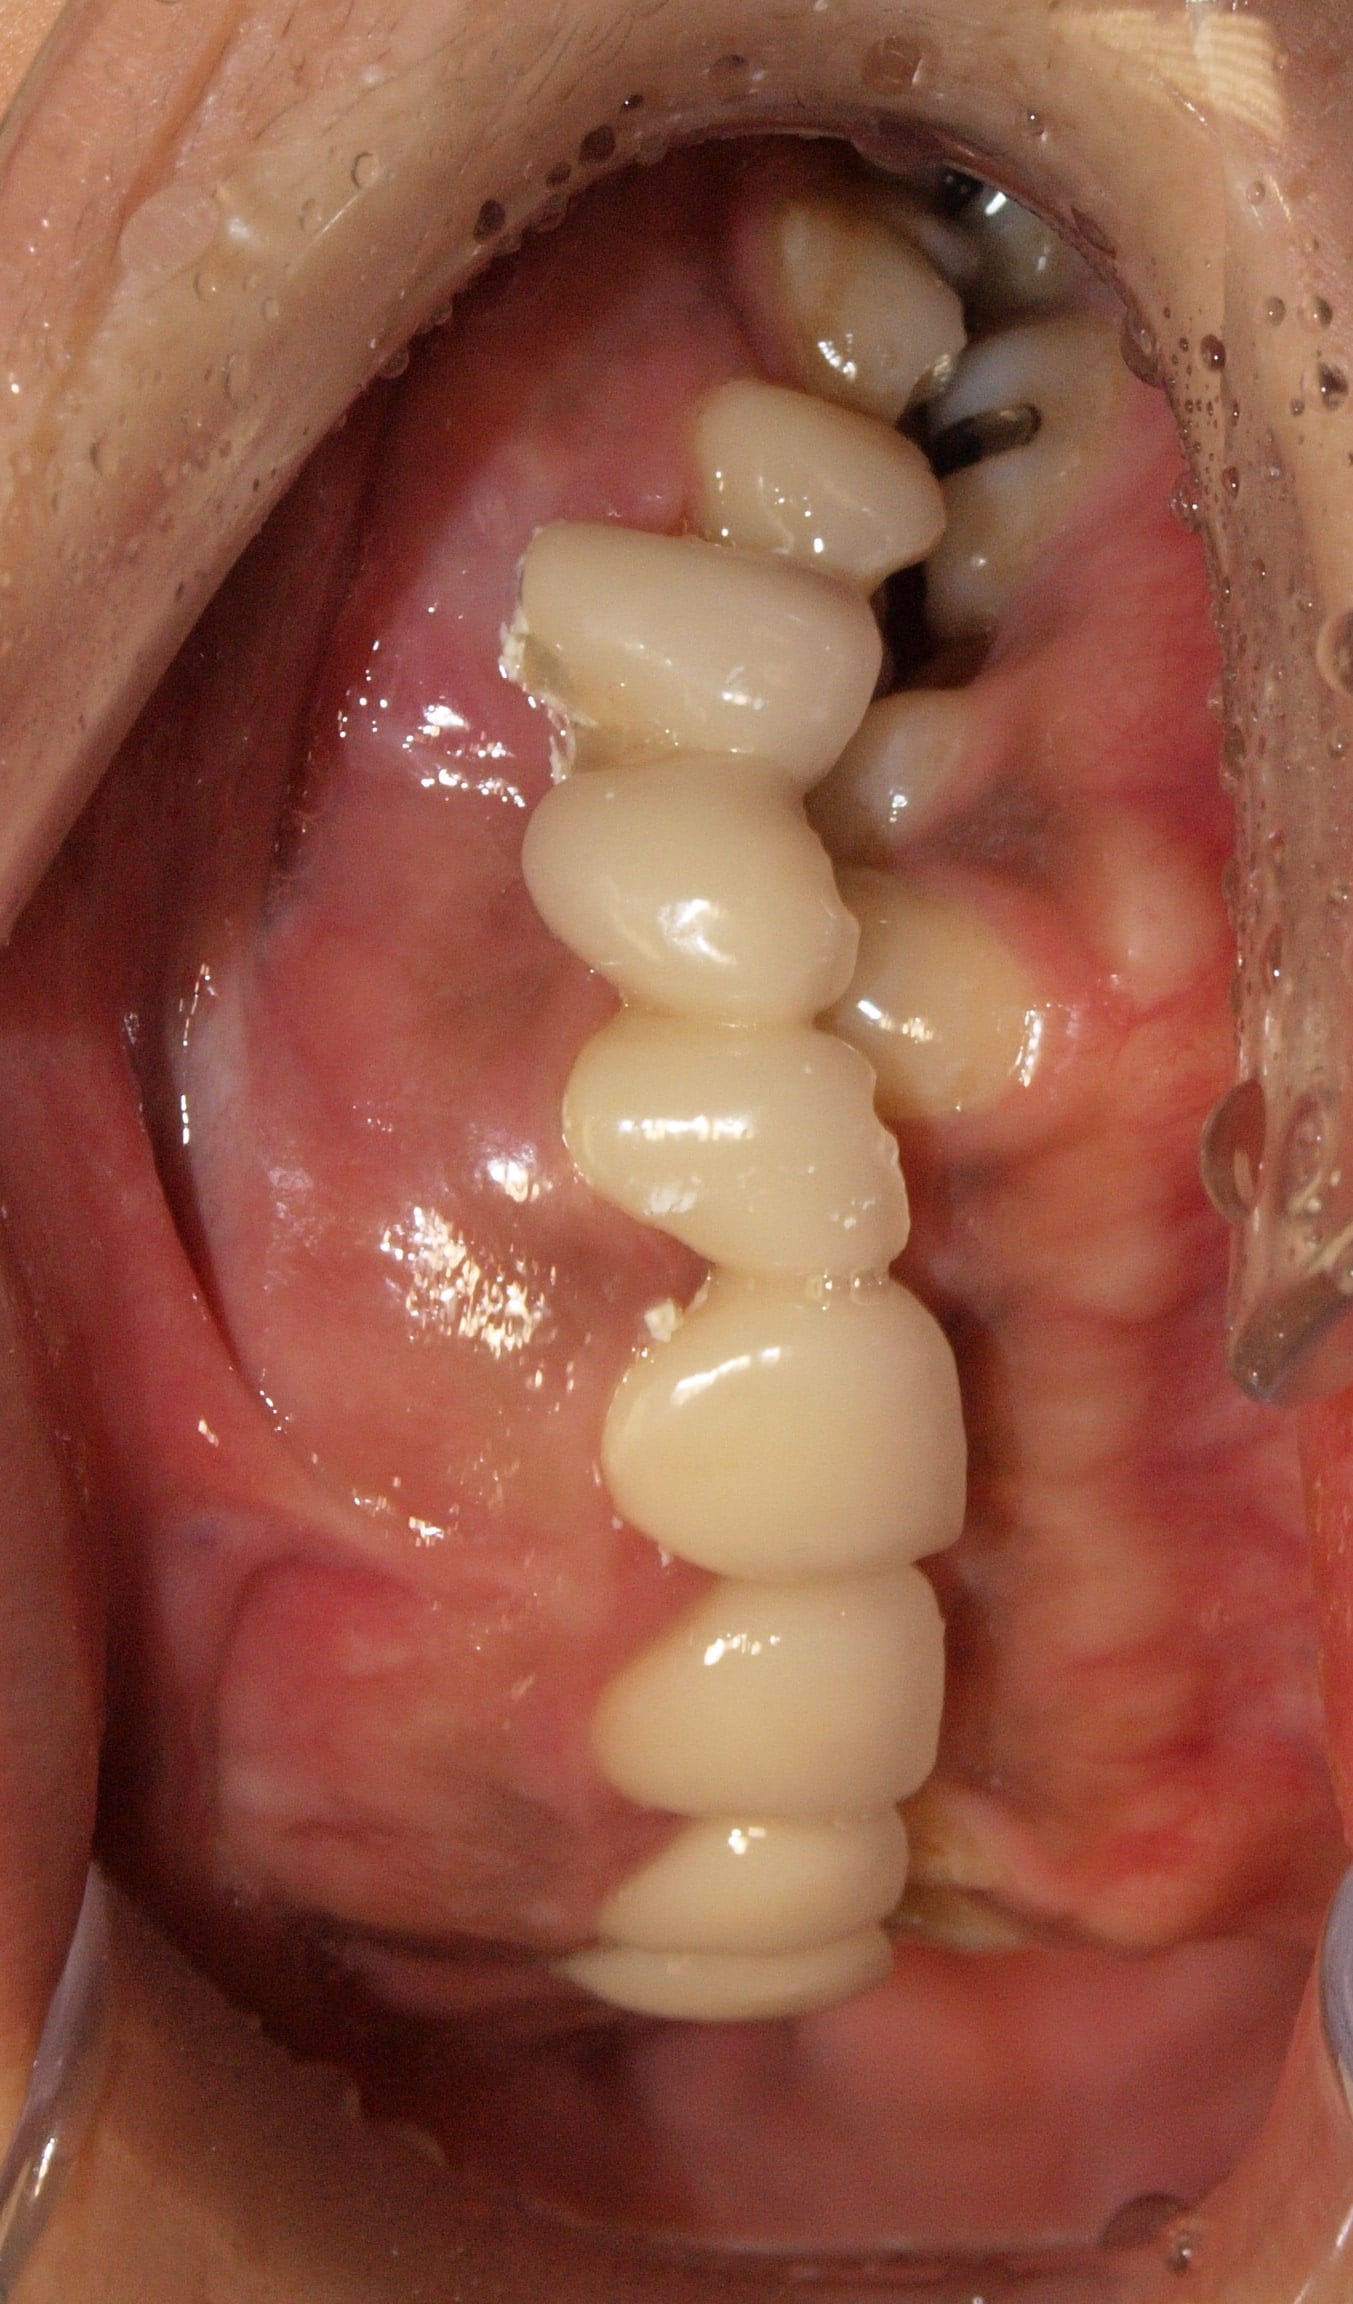

gauche

P1273390 o01gyf - Eugenol

Je pensais faire au moins des cales compo en posterieur pour liberer le secteur incisivo canin.

J'ai revu la patiente ce matin et en tous les cas la racine de 24 n'est pas du tout mobile. 21 et 22 non plus.